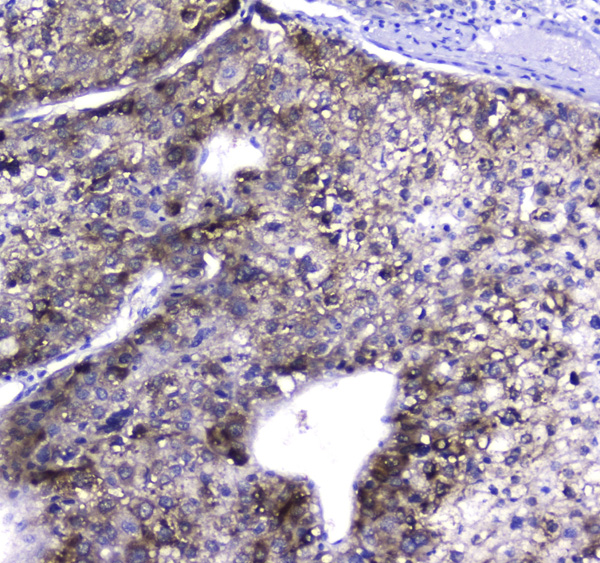

(Figure 2. IHC analysis of HGD using anti-HGD antibody (AAA124675).HGD was detected in paraffin-embedded section of human liver cancer tissue. Heat mediated antigen retrieval was performed in citrate buffer (pH6, epitope retrieval solution) for 20 mins. The tissue section was blocked with 10% goat serum. The tissue section was then incubated with 2ug/ml rabbit anti-HGD Antibody (AAA124675) overnight at 4 degree C. Biotinylated goat anti-rabbit IgG was used as secondary antibody and incubated for 30 minutes at 37 degree C. The tissue section was developed using Strepavidin-Biotin-Complex (SABC) with DAB as the chromogen.)